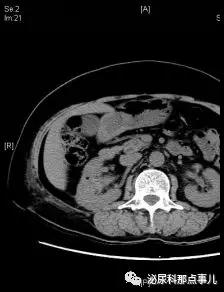

术前CT

术后CT